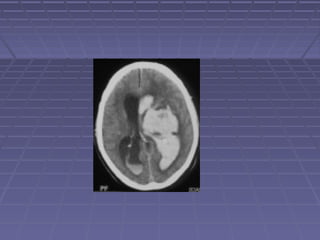

 TAC de cráneoTAC de cráneo si: persisten o aumentan lassi: persisten o aumentan las

manifestaciones clínicas, se sospechamanifestaciones clínicas, se sospecha

herniación, persiste la fiebre.herniación, persiste la fiebre.

 TC: hidrocefalia, lesiones vasculares,TC: hidrocefalia, lesiones vasculares,

tuberculomastuberculomas